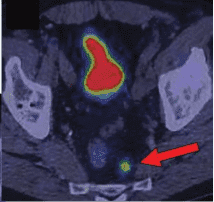

![]() | ![]() |

| Рисунок 4. Накопление радиофармпрепарата 68 Ga-DOTA-TATE пораженными лимфатическими узлами у пациента с НЭО прямой кишки. | |